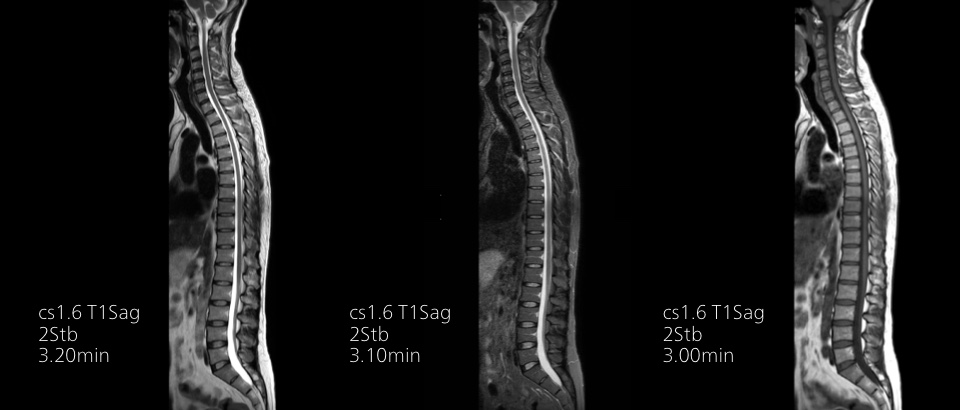

Turn images into answers – 50% faster

Put time on your side with Compressed SENSE to reduce scan time up to 50%2 with virtually equal image quality. Create exceptional MR images with 60% higher resolution for confident diagnosis.

Quality images for quality diagnoses

Our lightest Breeze coils bring extraordinary versatility to imaging challenging anatomies and the smallest joints. A large 55cm field-of-view and premium SNR add to the exceptional image quality.